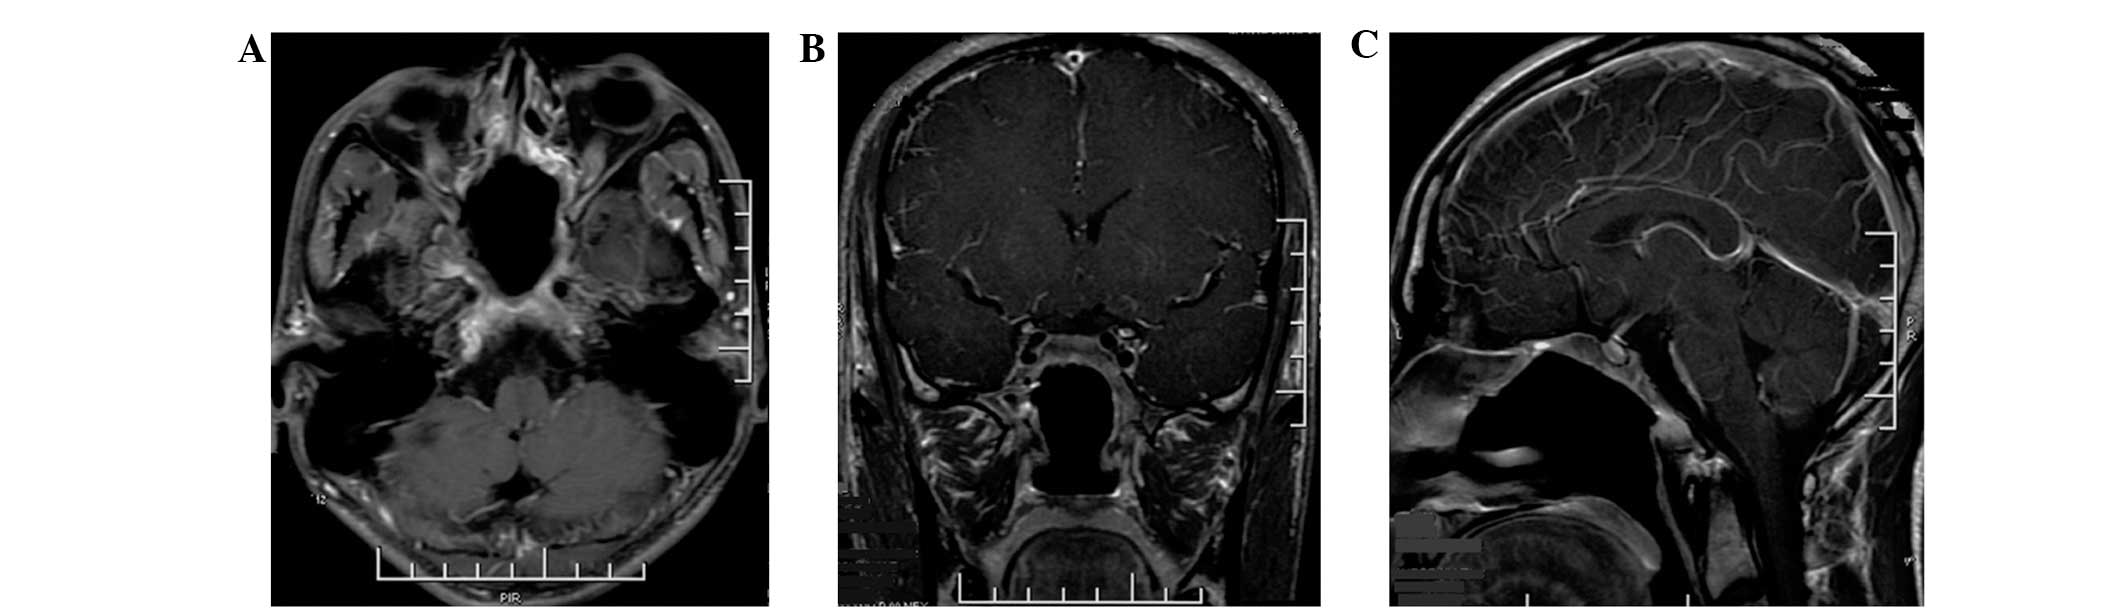

A 22-year-old male with a six month history of dull frontal headache did not receive any medical treatment or examination as the symptoms were tolerable. However, three days prior to admission, the headache worsened, and was localized to the right side. The patient developed secondary diplopia and facial numbness in the right maxilla area. On ophthalmological examination, the diplopia secondary to the left abducens nerve (CN VI) palsy was observed in the left eye. Examination of the cranial nerves revealed facial paresthesia along the distribution of maxillary (V2) divisions of the right trigeminal nerve (CN V). No abnormalities in vision, visual field, corneal reflexes, hearing or the power of masseters were identified and no papilledema was observed. The remaining motor and sensory neurological examinations, including cerebellar tests, were normal with full cooperation and orientation. Endoscopic nasal examination revealed a soft, friable mass, which bled when palpated in the posterior wall of the nasopharynx top. The laboratory evaluations including, complete blood count, biochemistry, analysis of tumor markers, thyroid and pituitary function tests and endocrinology examinations were normal, and the patient’s medical history was noncontributory. Magnetic resonance imaging (MRI) of the brain demonstrated an extensive soft-tissue density mass with an irregular shape and a clear boundary measuring 4.0×4.68×3.7 cm, involving the clivus, surrounding the cavernous sinuses on both sides and compressing the front of optic chiasm in the sphenoid sinus area of middle fossa. The posterior wall of the nasopharynx top was not involved. The tumor tissue was isointense on T1-weighted imaging (WI), T2WI and fluid-attenuated inversion recovery, and moderate homogenous enhancement was identified on the post contrast scan (Fig. 1). Due to the symptoms of the present illness and MRI imaging, chordoma and malignant tumor in clivus could not be excluded.

Figure 1

(A) Axial, (B) coronal and (C) sagittal section of T1-weighted magnetic resonance imaging with contrast revealing an expansive tumor originating from the clivus and surrounding both cavernous sinuses, compressing the front of optic chiasm in the sphenoid sinus area of the middle fossa.